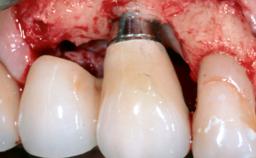

Surgical Management of Peri-Implantitis: Open-Flap Debridement with Seven-Year Follow-up After Treatment

This case describes both a surgical and an anti-infective approach for the management of peri-implantitis, including treatment of the entire dentition to eliminate any deep periodontal pockets that could serve as reservoirs for bacterial re-colonization at the implant site. A 65-year-old female patient was referred to the periodontist in 2013 for assessment and management of an infection at implant 12. On examination, probing depths at implant 12 were 11 mm with suppuration and bleeding on probing.